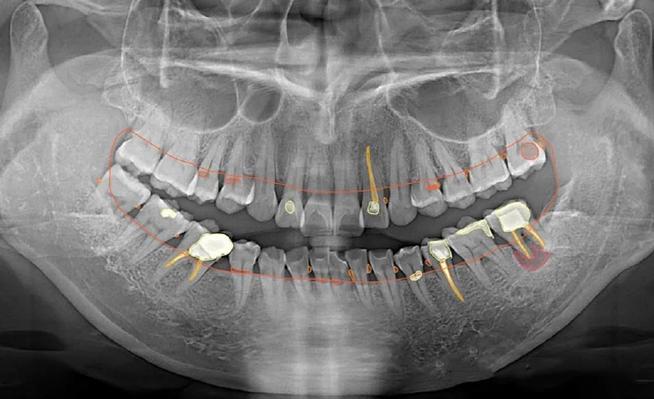

口腔正畸X光检查主要分为三类,各有其独特价值,曲面断层片(全景片)是最常用的基础检查,能一次性显示全口牙齿、牙槽骨、上下颌骨及部分颌面部结构,可观察是否有埋伏牙、多生牙、牙根吸收、牙槽骨骨密度异常等问题,辐射剂量低(约0.02mSv),相当于自然环境中2-3天的辐射量,适合常规筛查,头颅侧位片则是正畸诊断的“测量核心”,通过标记特定的解剖点(如蝶鞍、鼻根、上齿槽座点等),可定量分析上下颌骨的长度、宽度、高度比例,判断是否存在上颌前突、下颌后缩、面部不对称等问题,同时测量牙齿的倾斜角度、覆盖覆合程度,为矫治目标提供数据支持,CBCT(锥形束CT)则凭借三维成像优势,成为复杂病例的“精准导航”,能清晰显示牙根在颌骨内的位置、方向、形态,以及埋伏牙的萌出路径、骨量分布,适用于正颌手术前评估、种植体植入规划、疑难阻生牙拔除等场景,辐射剂量稍高(约0.1-0.3mSv),但单次检查仍在安全范围内,医生会严格掌握适应症。

这些检查的目的是多维度评估患者的口腔状况,牙齿层面,需明确牙齿数量(是否缺失、多生)、形态(畸形牙、过小牙)、位置(唇腭向错位、低位、高位)、牙根情况(弯曲、吸收、粘连)等,例如埋伏牙的定位能帮助医生设计开窗助萌方案;颌骨层面,需分析上下颌骨的发育是否协调(如下颌后缩导致的“地包天”)、骨量是否充足(如牙槽骨宽度不足影响种植)、是否存在代偿性生长(如上颌前突患者的下颌骨过度后缩);关节层面,通过观察颞下颌关节(TMJ)的间隙、髁突位置,排除关节疾病对正畸治疗的影响,避免因关节紊乱导致治疗失败;牙槽骨层面,需评估牙槽骨的厚度、密度,判断是否具备足够的支抗支持移动牙齿,防止骨开窗、骨开裂等并发症。

| CBCT | 三维显示颌骨细微结构、牙根位置、骨量;复杂病例(正颌、种植)评估 | 三维高分辨率,精准定位 | 辐射较高,成本较高 |